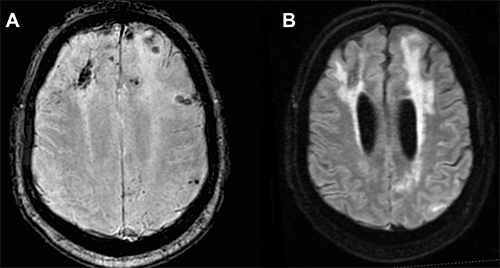

MRI scans of a patient with CAA.

(Image courtesy of Current Treatment Options in Neurology).

MRI is essential to make a diagnosis and contrast enhancement is helpful but not required. MRI scans generated using fluid-attenuated inversion recovery (FLAIR) sequencing show white matter hyperintense lesions extending to the immediately subcortical white matter and one or more of the following hemorrhagic lesions:

- Cerebral macrohemorrhage

- Cerebral microhemorrhage

- Cortical superficial siderosis